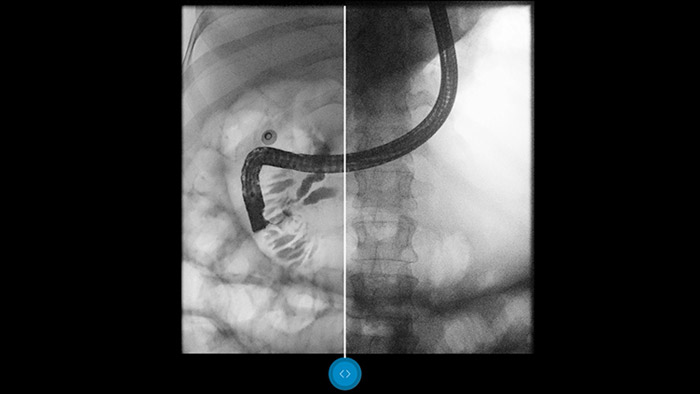

Vergelijk beelden naast elkaar met een conventionele beeldverwerking en bekijk zelf de voordelen.

Dynamic UNIQUE-beeldverwerkingssoftware harmoniseert het contrast. Daarnaast worden vage details verbeterd en zorgt de software voor een uniforme beeldkwaliteit, waardoor het verschil tussen botten en zacht weefsel duidelijk te zien is.